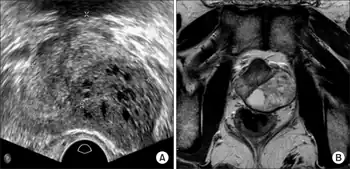

a)Ultrasound shows heterogeneous echogenic lesion in peripheral zone of prostate b) MRI left lobe of the prostate without extracapsular extension